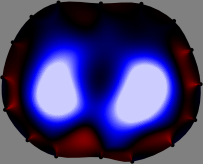

Refer to caption

Figure 2: Fidelity-embedded regularization method. (Left bottom) Correlations between four different column vectors (𝐒ksubscript𝐒𝑘{\bf S}_{k}) and all the remaining column vectors (𝐒subscript𝐒{\bf S}_{\ell}) are visualized. (Right bottom) Performances of the proposed fidelity-embedded regularization method for λ=𝜆\lambda=\infty are shown by numerical simulations.

To explain the FER method, we closely examine the correlations among column vectors of the sensitivity matrix 𝕊𝕊\mathbb{S}, described in Fig. 2. The correlation between 𝐒ksubscript𝐒𝑘{\bf S}_{k} and 𝐒subscript𝐒{\bf S}_{\ell} can be expressed as

for i=1,,16𝑖116i=1,\cdots,16[23]. This shows that the column vector 𝐒ksubscript𝐒𝑘{\bf S}_{k} is like an EEG (electroencephalography) data induced by dipole sources with directions uj,j=1,,16formulae-sequencesubscript𝑢𝑗𝑗116\nabla u_{j},j=1,\cdots,16 at locations ΔksubscriptΔ𝑘\Delta_{k}. Given that two dipole sources at distant locations produce mutually independent data, the correlation between 𝐒ksubscript𝐒𝑘\mathbf{S}_{k} and 𝐒subscript𝐒\mathbf{S}_{\ell} decreases with the distance between ΔksubscriptΔ𝑘\Delta_{k} and ΔsubscriptΔ\Delta_{\ell}. Fig. 2 shows a few images of the correlation 𝐒k,𝐒(|𝐒k||𝐒|)1subscript𝐒𝑘subscript𝐒superscriptsubscript𝐒𝑘subscript𝐒1\left\langle\mathbf{S}_{k},\mathbf{S}_{\ell}\right\rangle(|\mathbf{S}_{k}||\mathbf{S}_{\ell}|)^{-1} as a function of \ell for four different positions ΔksubscriptΔ𝑘\Delta_{k}. The correlation decreases rapidly as the distance increases. In the green regions where the correlation is almost zero, 𝐒subscript𝐒{\bf S}_{\ell} is nearly orthogonal to 𝐒ksubscript𝐒𝑘{\bf S}_{k}.